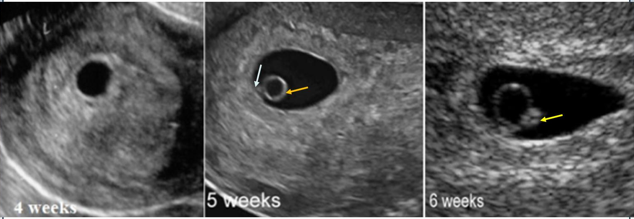

Thại kỳ bình thường sẽ có độ dài là 40 tuần (280 ngày) kể từ ngày bắt đầu của kỳ kinh cuối cùng. Ngày kinh cuối cùng là một điểm mốc để đánh dấu sự kiện có thai. Tuần thứ 3 là khoảng thời gian xảy ra hiện tượng thụ tinh, vận chuyện trứng đã thụ tinh vào buồng tử cung cho đến khi phôi thoát màng và bắt đầu tiến triển làm tổ. Tuần thứ 4 là khoảng thời gian làm tổ. Vào tuần thứ 5,phôi được cấu tạo bởi 3 lớp tế bào: ngoại bì phôi, trung bì phôi và nội bì phôi. Tuần thứ 6, bắt đầu có hoạt động của tim phôi. Tuần thứ 7, nhìn thấy phôi trên siêu âm. Tuần thứ 8 và thứ 9, bớt uốn cong và rởt thành dạng thẳng. Chiều dài phôi phát triển tuyến tính, với tốc độ phát triển khoảng 1m mỗi ngày. Kể từ thời điểm này trở đi, phôi thai chính thức được gọi là thai nhi.

Hình 1. Quá trình phát triển phôi thai và thai nhi.

Hình 2. Một số hình ảnh siêu âm ở tuần thứ 4, thứ 5, thứ 6 từ trái sang phải.